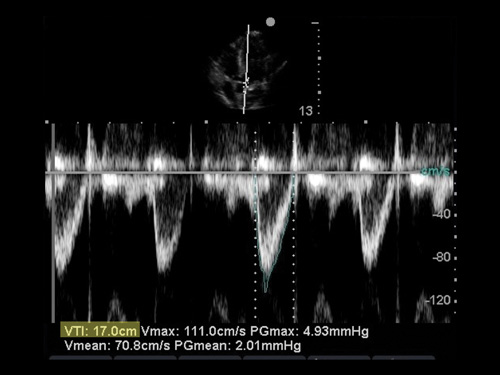

- VTI (tích phân thời gian vận tốc) bằng Doppler xung tại vị trí van động mạch chủ(đường ra thất trái) ở mặt cắt 5 buồng ở mỏm tim.

- Vẻ đường vòng quanh sóng âm

- Ghi nhận VTI